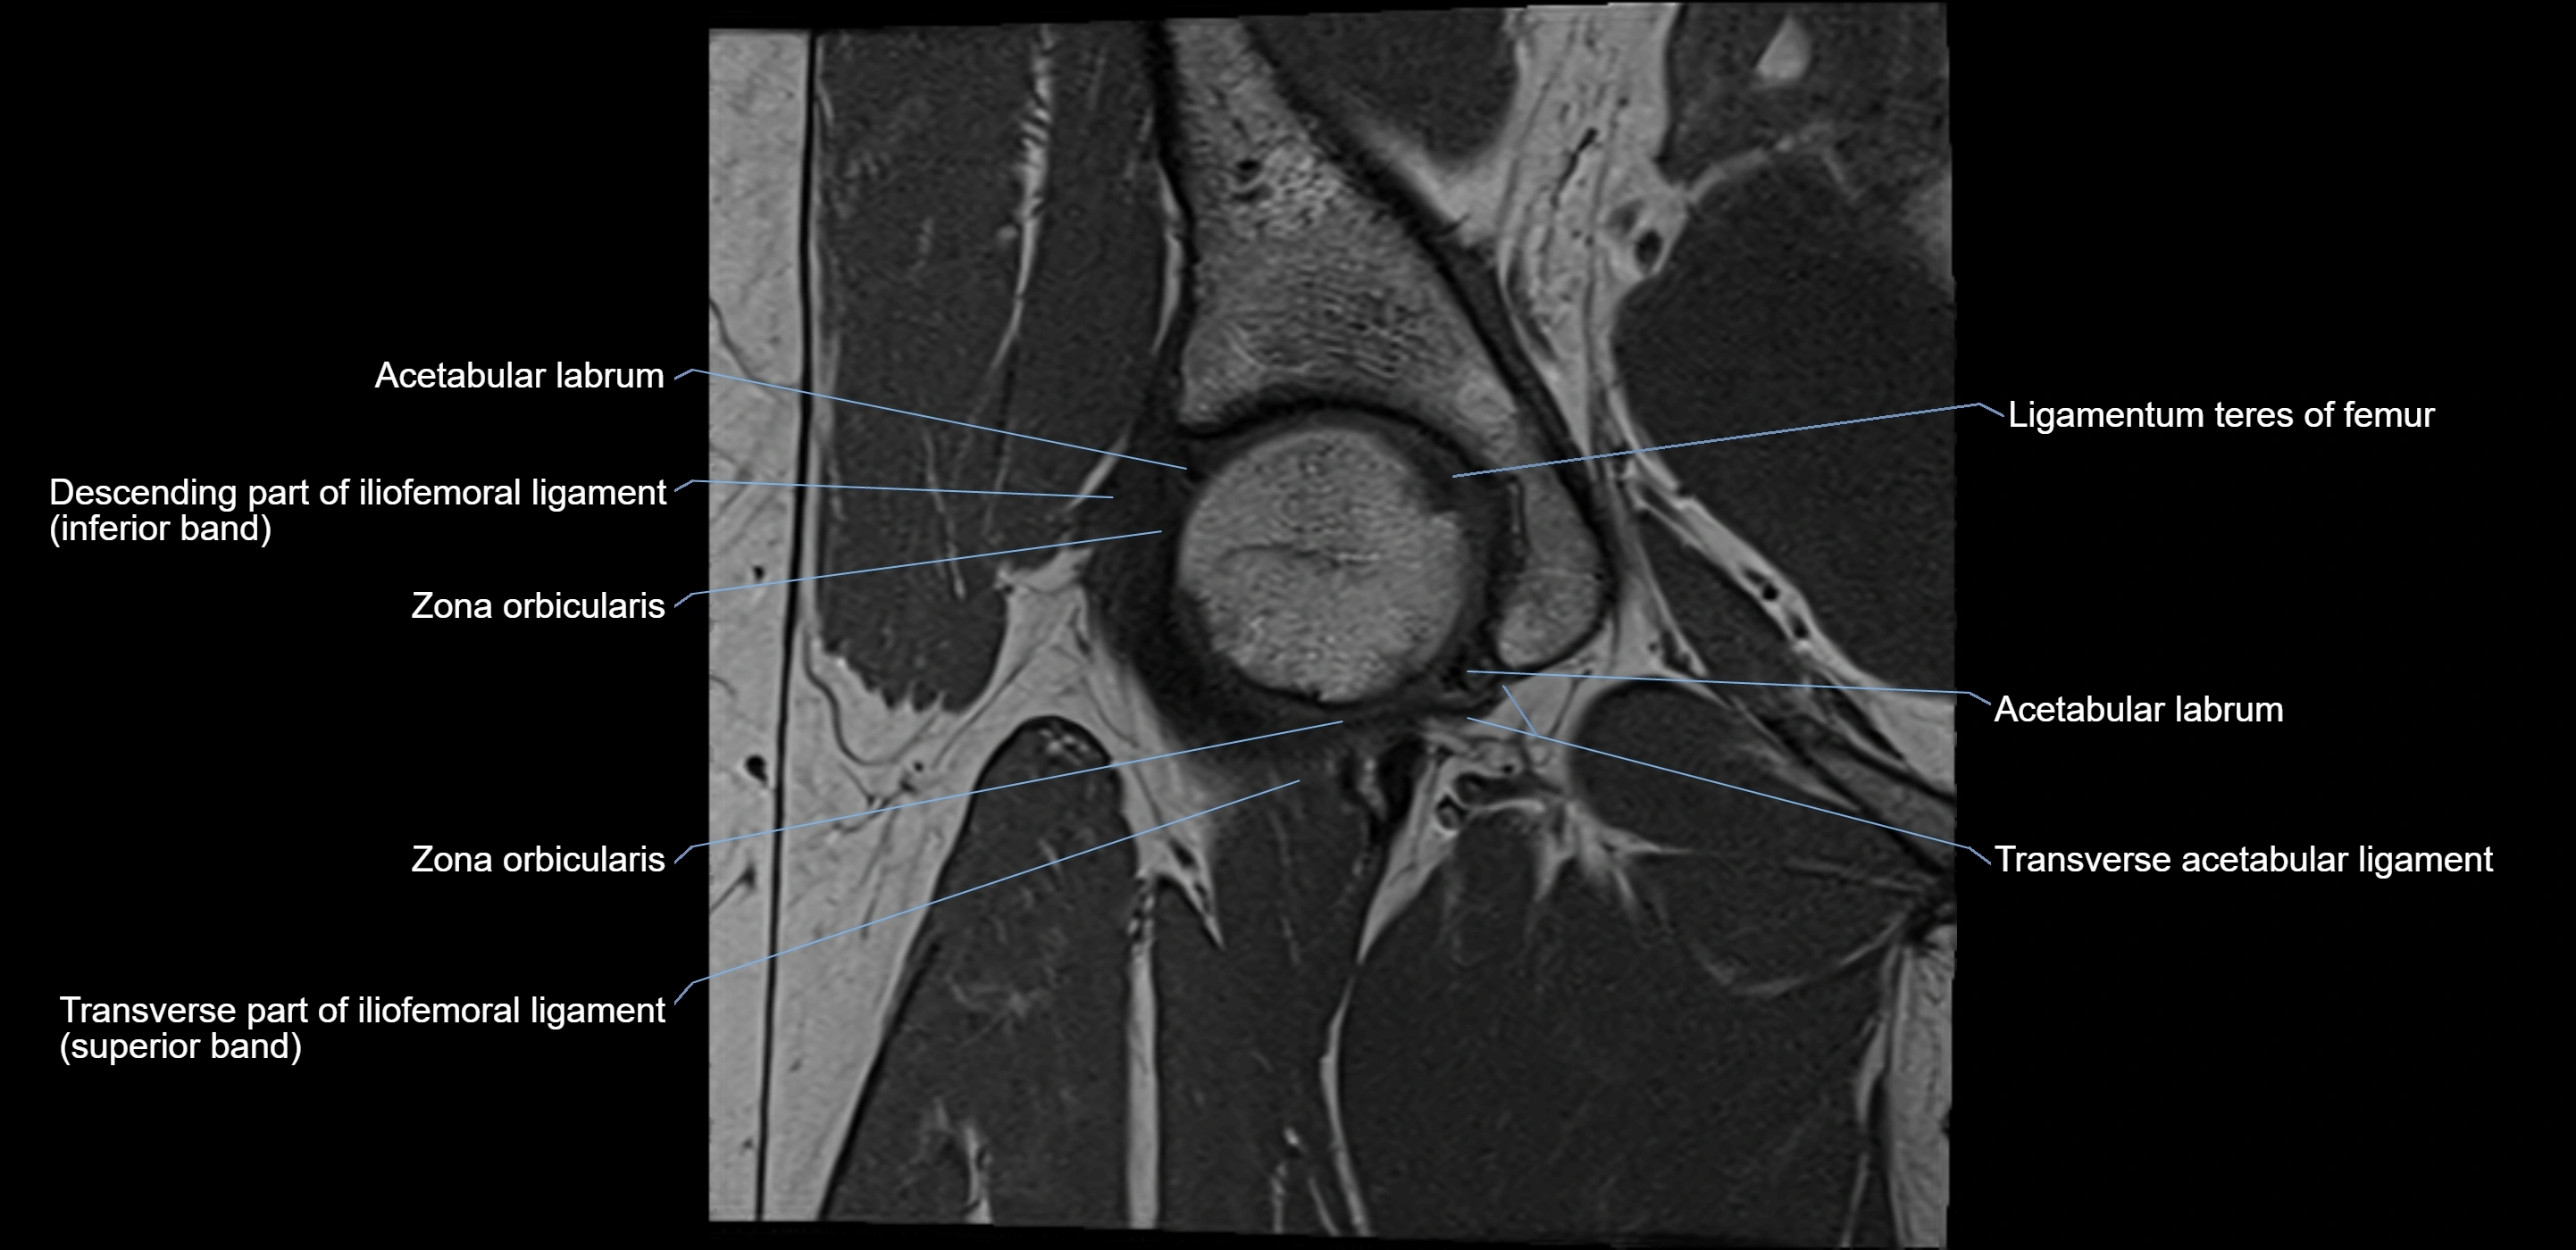

MRI Appearance

T1-weighted images:

• Labrum: low signal intensity (dark)

• Surrounded by intermediate signal joint fluid (bright on arthrogram)

• Tears: linear or focal areas of intermediate-to-high signal interrupting labral continuity

T2-weighted images:

• Joint fluid: bright, making labral tears visible as fluid extending into or around labrum

• Degeneration: may show areas of increased signal within labrum

MRI image

image